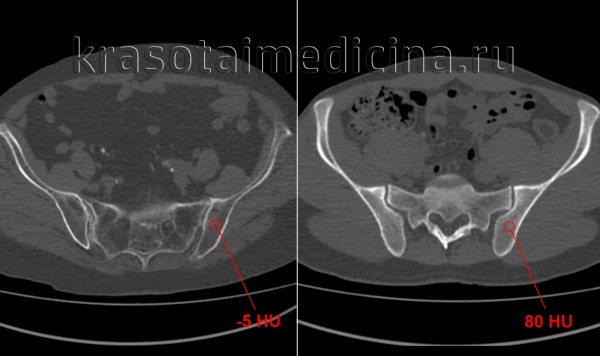

КТ таза. Выраженное разрежение трабекулярной структуры и жировая дегенерация костей таза (слева) у пожилой женщины, справа для сравнения норма у молодого мужчины.